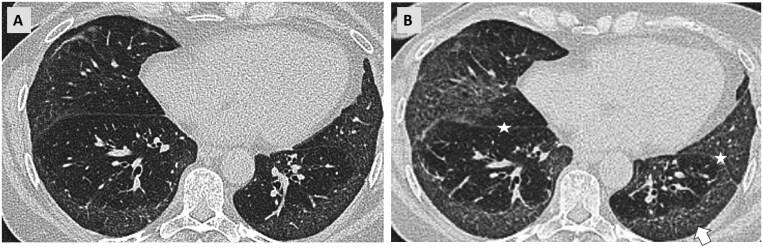

A subset of patients with interstitial lung diseases (ILDs) experiences disease progression despite standard treatment protocols. Similar to idiopathic pulmonary fibrosis, the archetype of progressive fibrotic ILDs, these patients exhibit worsening clinical symptoms, declining lung function, and progressive radiological changes, often resulting in shortened survival. This progressive disease pattern is classified under the term progressive pulmonary fibrosis or progressive fibrosing ILD. Radiological imaging, particularly high-resolution computed tomography (HRCT), is integral to diagnosing ILDs and plays a critical role within multidisciplinary ILD boards. HRCT is instrumental in identifying patients at a higher risk for disease progression and may provide valuable prognostic insights. Additionally, serial imaging is essential for detecting progression over time. While visual assessment remains the primary method for evaluating disease advancement, emerging quantitative techniques, including those utilizing machine learning, are currently undergoing validation.

尽管采用了标准治疗方案,仍有一部分间质性肺疾病(ILD)患者病情进展。与进行性纤维化ILD的原型特发性肺纤维化类似,这些患者表现出临床症状恶化、肺功能下降和影像学改变进展,常导致生存期缩短。这种进行性疾病模式归类为进行性肺纤维化或进行性纤维化ILD。放射影像学,尤其是高分辨率计算机断层扫描(HRCT),对于ILD的诊断不可或缺,在多学科ILD诊疗团队中发挥着关键作用。HRCT有助于识别疾病进展风险较高的患者,并可能提供有价值的预后信息。此外,系列成像对于检测随时间的进展至关重要。虽然视觉评估仍然是评估疾病进展的主要方法,但包括利用机器学习的技术在内的新兴定量技术目前正在进行验证。